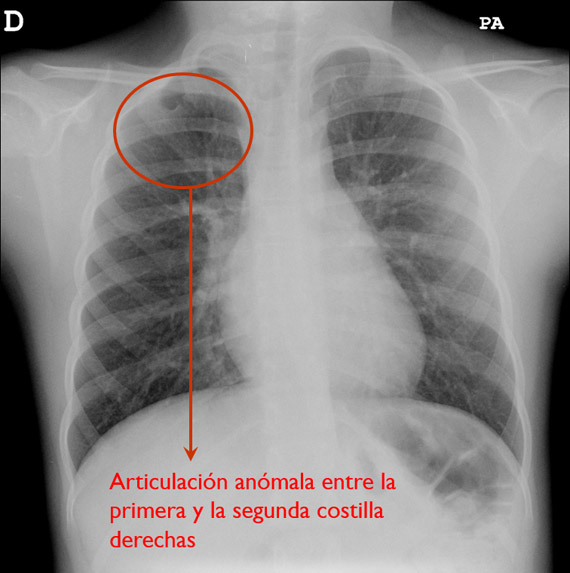

• Pared torácica: debemos buscar fracturas, malformaciones u otras lesiones óseas destructivas que puedan ser indicadoras de patología como osteomielitis o tumores óseos. No hay que olvidarnos de los tejidos blandos: piel, grasa y músculo.